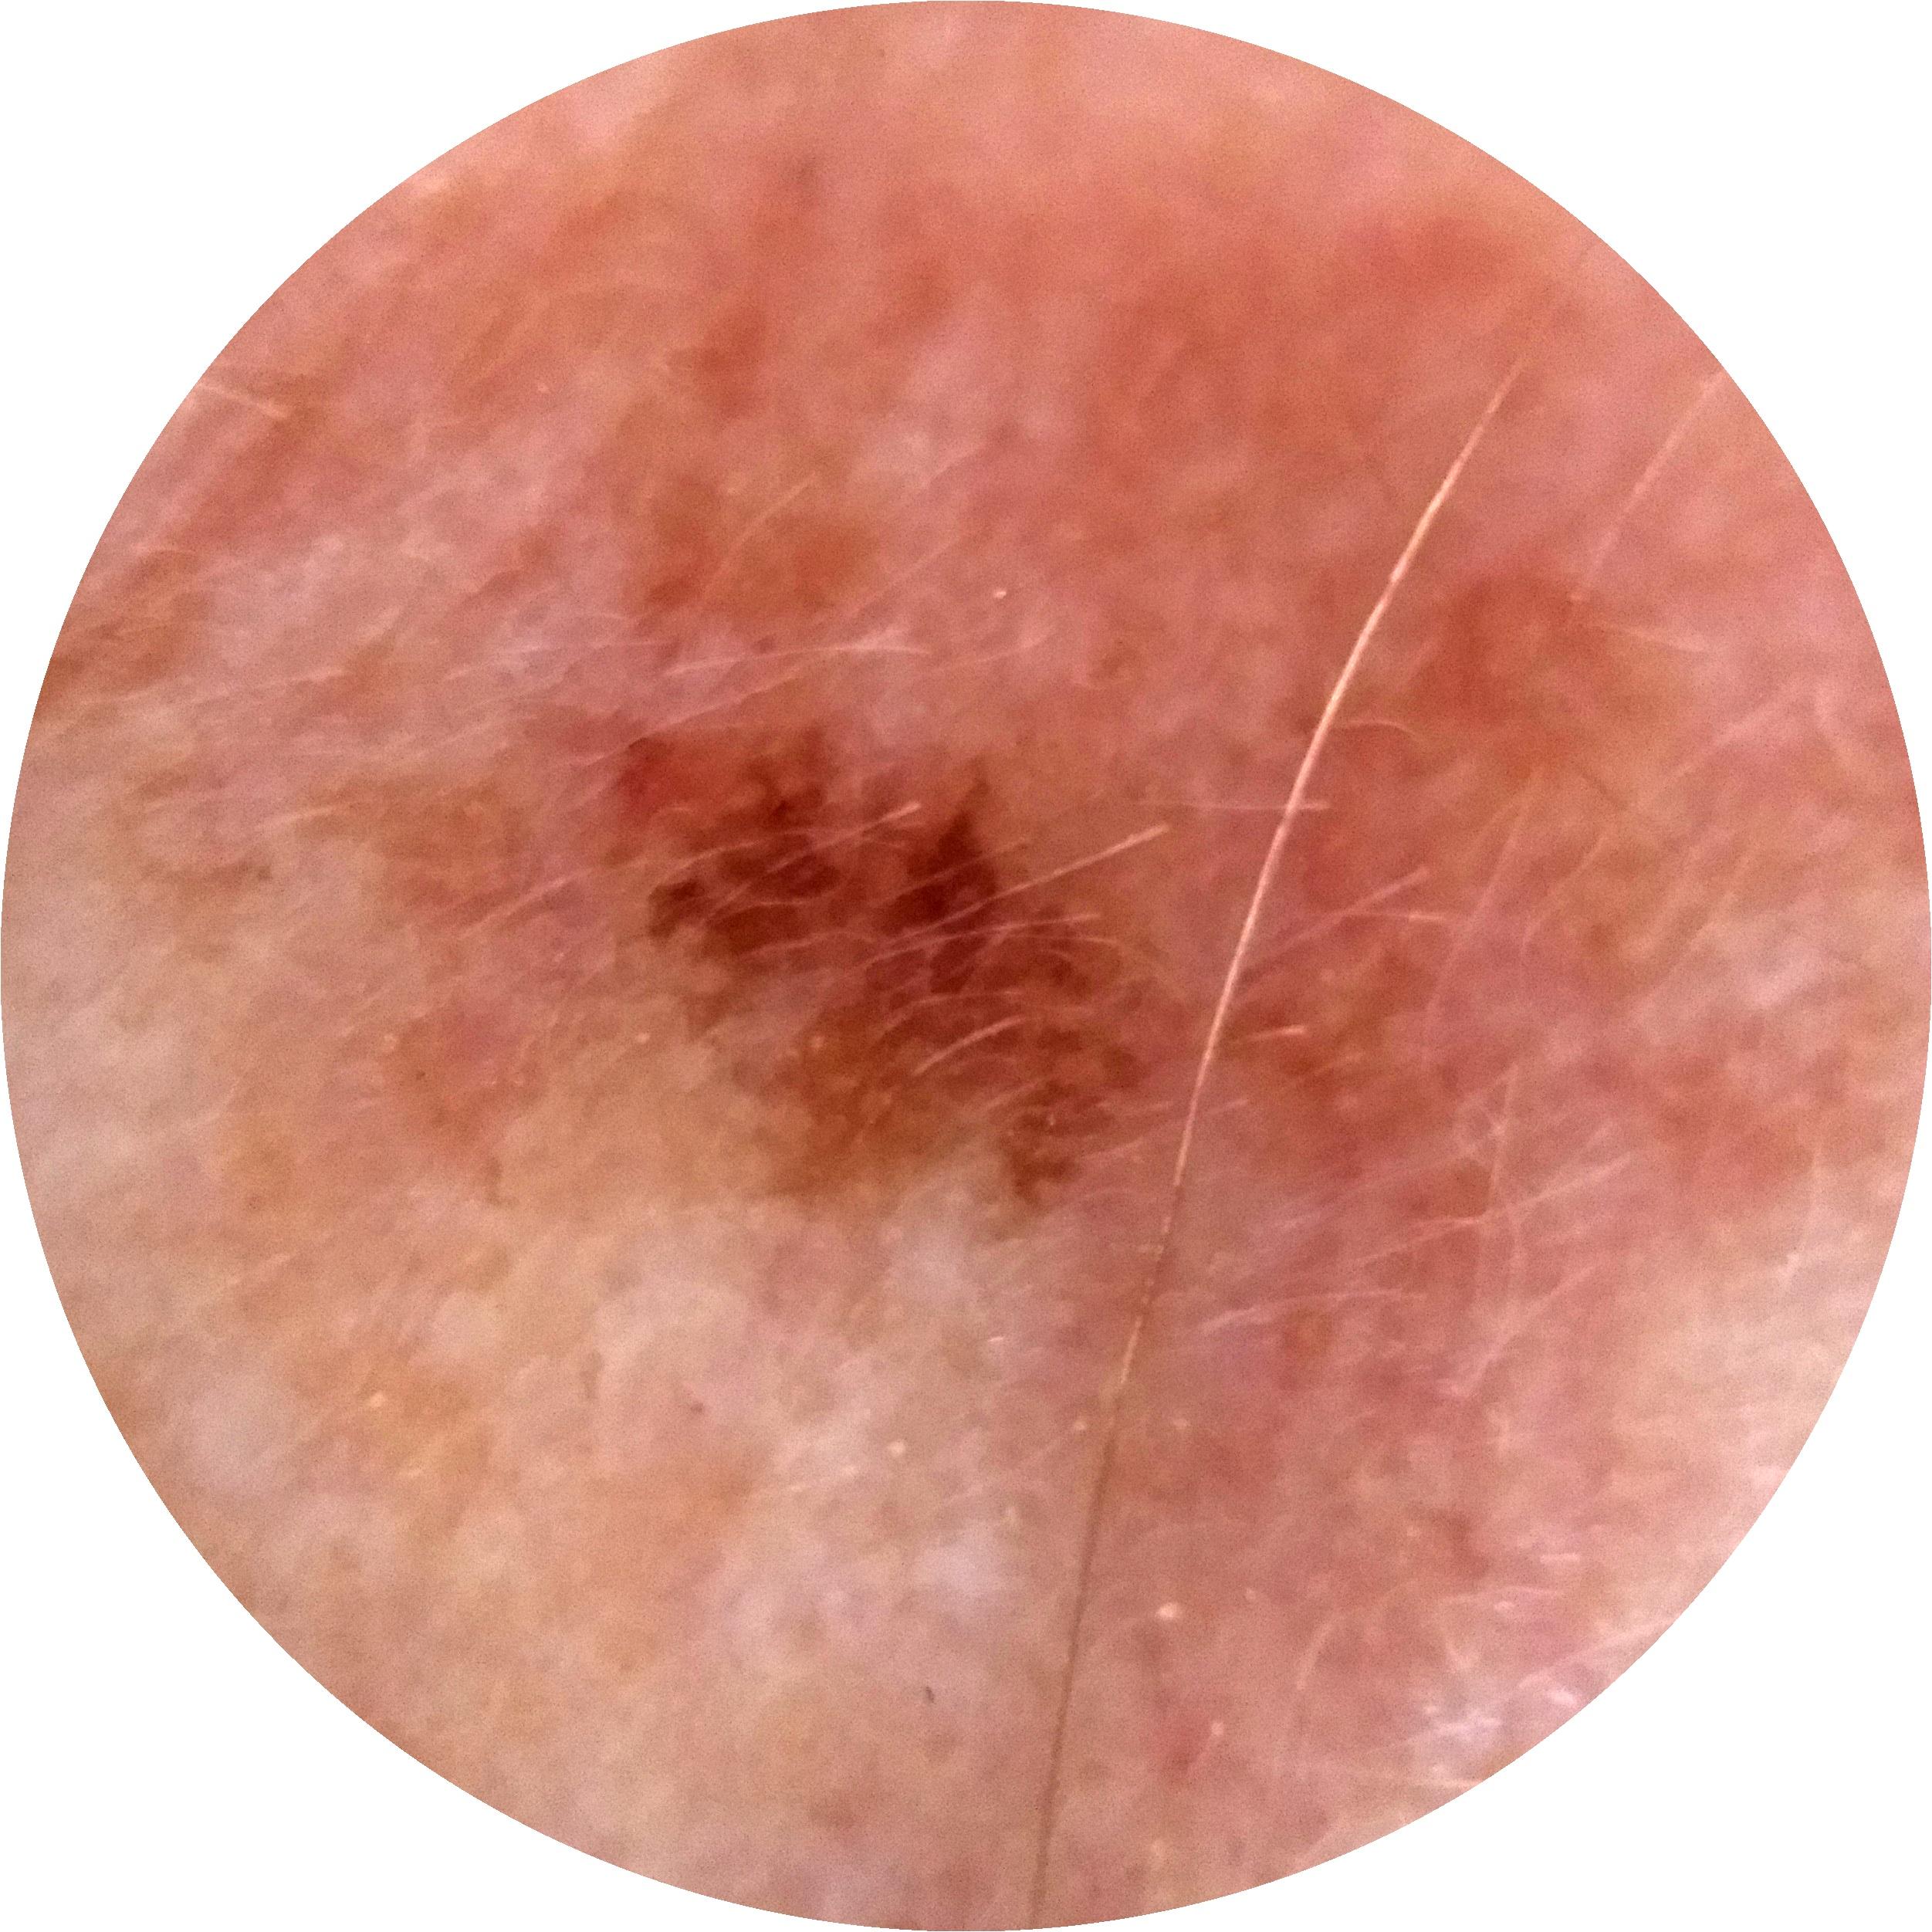

ISIC_7354512

image_type dermoscopic

lesion_id IL_4454105